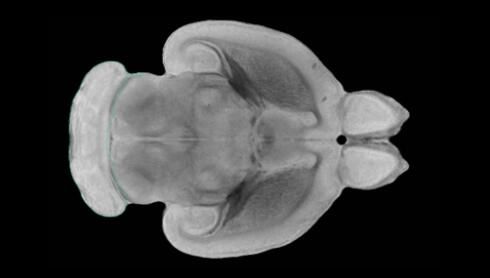

隨著機(jī)體年齡增加,肌肉和關(guān)節(jié)都會(huì)變得僵硬,這就會(huì)使得日?;顒?dòng)變得更加困難,本文研究表明,我們的大腦也是如此,與年齡相關(guān)的大腦僵硬對(duì)大腦干細(xì)胞的功能或許有著重要影響。文章中,研究人員對(duì)年輕和老化大鼠的大腦進(jìn)行研究闡明了年齡相關(guān)大腦僵硬對(duì)少突膠質(zhì)前體細(xì)胞(OPCs,oligodendrocyte progenitor cells)功能的影響。OPCs是一類(lèi)對(duì)維持正常大腦功能非常重要的大腦干細(xì)胞,其對(duì)于髓磷脂的再生也非常重要,髓磷脂是神經(jīng)組織周?chē)闹厩?,在多發(fā)性硬化癥中髓磷脂的再生常常會(huì)被損傷,機(jī)體老化對(duì)這些細(xì)胞的影響常常會(huì)誘發(fā)多發(fā)性硬化癥的發(fā)生,這些細(xì)胞的功能在老化的健康人群中同樣會(huì)下降。

為了確定老化OPCs的功能缺失是否可以被逆轉(zhuǎn),研究人員將來(lái)自老化大鼠機(jī)體的老化OPCs轉(zhuǎn)移到了年輕大鼠柔軟的海綿狀大腦組織中去,值得注意的是,這些老化的大腦細(xì)胞能夠重新恢復(fù)活力,其行為非常像年輕更加強(qiáng)壯的細(xì)胞。這項(xiàng)研究中,研究人員在實(shí)驗(yàn)室中開(kāi)發(fā)出了具有可變僵硬程度的新型材料,并在受控環(huán)境下研究這些材料的生長(zhǎng)及其對(duì)大鼠大腦干細(xì)胞的影響,這些材料能被工程化改造具有和年齡或老化大腦相似的柔軟程度。

為了深入理解大腦組織柔軟和僵硬影響細(xì)胞行為的分子機(jī)制,研究人員對(duì)細(xì)胞表面一種名為Piezo1的蛋白質(zhì)進(jìn)行了分析,該蛋白質(zhì)能“告知”細(xì)胞其周?chē)沫h(huán)境為柔軟或僵硬。研究者Kevin Chalut說(shuō)道,我們發(fā)現(xiàn),當(dāng)在僵硬材料上促進(jìn)年輕具有功能性的大鼠干細(xì)胞時(shí),這些細(xì)胞就會(huì)表現(xiàn)出功能異常,并失去其再生的能力,實(shí)際上其行為與老化細(xì)胞相似。當(dāng)將老化的大腦細(xì)胞在柔軟材料上生長(zhǎng)時(shí),其功能就會(huì)表現(xiàn)得像年輕細(xì)胞一樣,換句話(huà)說(shuō),其能夠重新恢復(fù)年輕的活力。